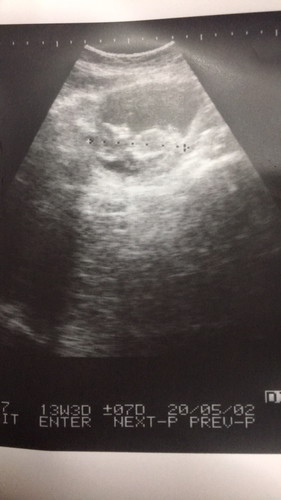

ตัวน้อยดิ้นกี่เดือน

อยากทราบว่าแม่ๆตัวน้องเริ่มดิ้นกันตั้งแต่กี่เดือนคะ เรา 13+ สัปดาห์ รู้สึกว่าตอดๆ กัวคิดไปเอง ?